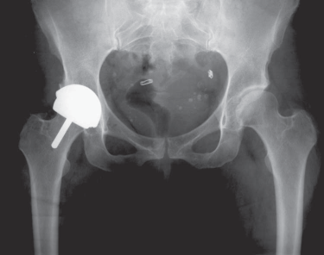

术后5天,脱位

术后4月,再一次脱位